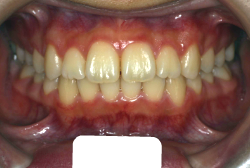

「歯並びの凸凹を直したい」という主訴で来院したケースです。診断の結果、たしかに「叢生」という隙間が足りないと言うことが原因の凸凹症例でした。

しかし、それ以上に問題なのは「前歯の噛み合い方が深すぎる」という症状で、初診の歯の正面写真を見ると下の前歯が全く見えません。こういう症状を矯正学では「過蓋咬合(かがいこうごう)」と言います。過蓋咬合を放置すると、将来的に顎関節に悪影響を与えるとされており、顎関節症の原因因子の一つです。また下の前歯の先端が、上の前歯の裏側の歯茎と強く接触するため、歯周病の原因にもなります。

検査の結果、凸凹が軽症なため非抜歯で矯正すること可能と判断、マルチブラケット装置にて治療しました。治療後は歯並びが綺麗になっただけでなく、噛み合わせ的にも正しい状態が確立しています。